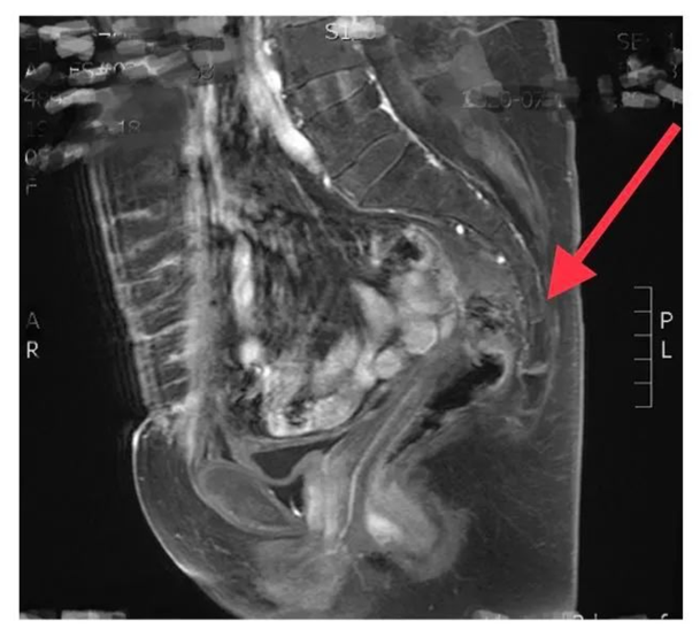

手术由傅教授亲自主刀,使用3D腹腔镜进行操作,由于此前的两次直肠手术以及患者既往的子宫切除病史,下腹部粘连非常严重,腹腔镜赖以操作的戳卡都难以打入腹腔,“水帘洞”般的视野使得手术的难度变得很大,手术者等同于在“迷雾”中操作。然而拥有几十年结直肠癌手术经验的傅教授并没有被眼前的景象难倒,他从容地操作电铲,利用仅有的一个戳卡孔,依靠着自己对腹腔解剖结构的熟悉,在“迷雾”中杀出了一条血路,盆腔终于显露在了眼前。

然而困难并没有就此结束,多次手术的创伤以及吻合口瘘的炎症反应使得盆腔的脏器粘连更严重。本次手术的目的是切除掉已经狭窄的吻合口段的直肠,并将近端的直肠和远端再次吻合,在这样的粘连背景下,已经接受过两次手术的直肠和盆腔的其他重要血管、神经融合成了一个“蝉蛹”,手术的难度极大。傅教授依旧没有慌乱,拿起了高频电铲熟练果断地切开了一层又一层包裹在一起的组织,并巧妙地避开了附近的输尿管、生殖血管、神经,如在“迷雾”中“百发百中”的神枪手,最终分离出了直肠,完成了狭窄吻合口的切除和再吻合。虽然整个手术难度极大,耗时5个小时,但是傅教授全程都十分的冷静沉着,整个手术显得比较顺利。